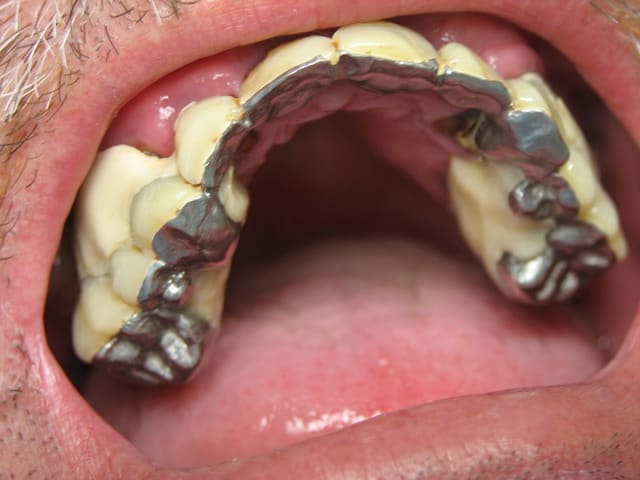

recommandé par une patiente... son amie...

la bridge "amovible"... "réparé au centre médical"...

motif de la consultation: "une infection de la dent du fond" commencée à traiter par 1 clamoxyl, en automédication...